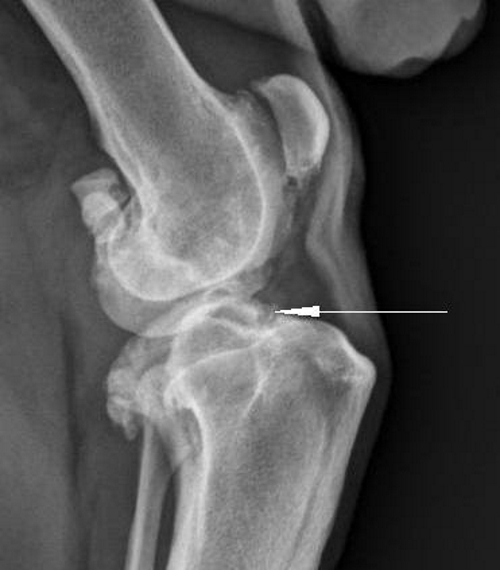

- рентгенологическим данным по Косинской;

Согласно классификации Косинской выделяют три степени ДОА:

- Первая степень: минимальные изменения, ограничения в движении практически отсутствуют, суставная щель немного сужена, остеофиты только начинают формироваться.

- Вторая степень: движения сустава ограничены, он функционирует только в определенных направлениях. Любое движение вызывает хруст, слышимый на расстоянии. Суставная щель сужена в 2-3 раза по сравнению с нормой, костные шпоры увеличены, появились эпифизарные кисты, мышцы умеренно атрофированы.

- Третья степень ДОА: отсутствует синовиальная жидкость, выражены уплотнение и деформация сустава. Движения ограничены до 5-7 градусов, суставная щель полностью закрыта, что приводит к анкилозу. Шпоры распространены по всему суставу, на рентгене могут быть видны обломки хряща и кисты в кости. Полное сращение сустава называется анкилозом и соответствует четвертой степени ДОА.